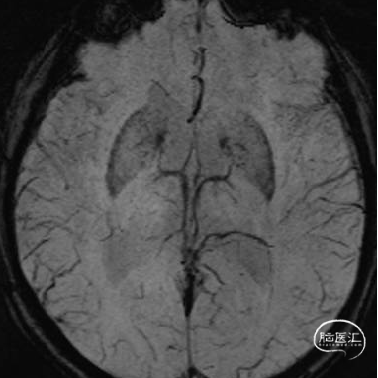

头部DWI、Flair

头部SWI